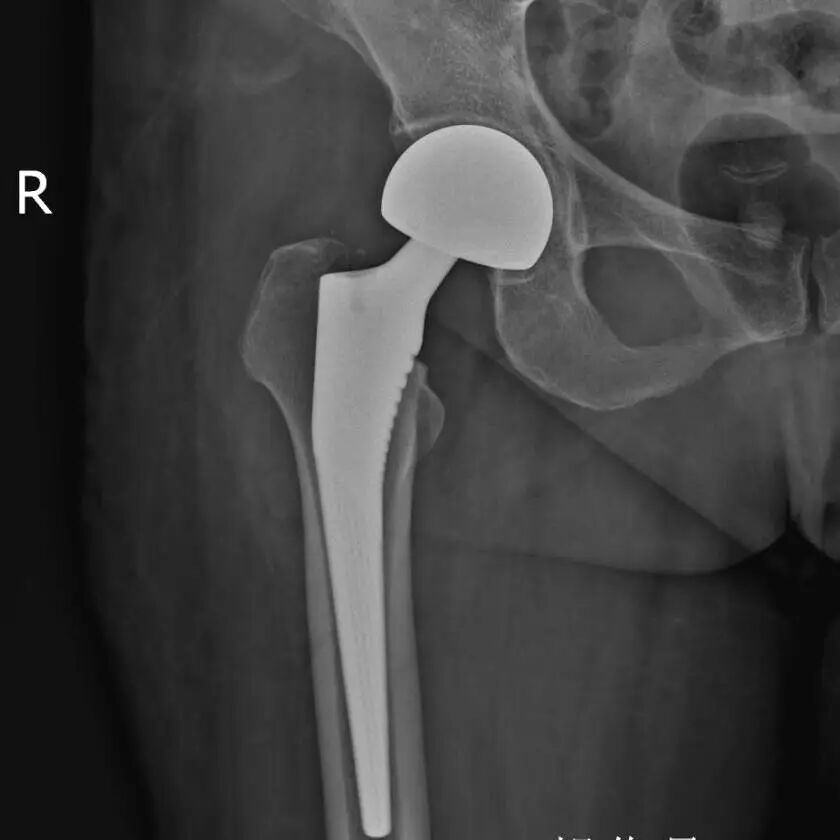

孙奶奶检查出来右股骨颈骨折,合并高血压,需谨慎处理。骨科主任孙大川查看后,与孙奶奶家属积极沟通:孙奶奶年纪较大,右侧股骨颈骨折并且是头下型,应早期手术治疗早期下地活动,以避免长期卧床带来的褥疮、深静脉栓塞等一系列危及生命的卧床并发症。人工全髋关节置换手术是目前最佳的治疗方案,能够提高患者生活质量、延续患者生命、恢复肢体功能。

家属认可其方案后,在九院专家朱振安教授的指导下,孙大川主任与叶茂医师共同对孙奶奶实施了“右股骨头置换术”。

凭借丰富的经验和娴熟的技术,手术仅耗时40分钟便顺利完成。

术后X光片显示假体位置精准,关节对位良好